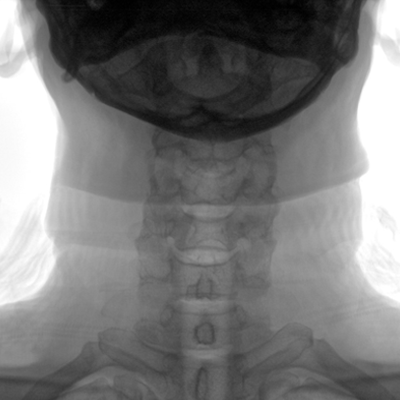

動(dòng)態(tài)板C形臂 開(kāi)啟清晰影像新篇章 PLX118F

臨床適用科室:骨科、普通外科、矯形外科、創(chuàng)傷外科、泌尿外科、脊柱外科、疼痛外科、消化科、婦科等科室。

大尺寸動(dòng)態(tài)平板探測(cè)器,高DQE、低噪聲、圖像清晰。采用多分辨率圖像增強(qiáng)處理技術(shù),不同部位不同圖像處理算法,滿足客戶多樣化的需求。

采用智能變頻脈沖透視技術(shù),優(yōu)化圖像質(zhì)量的同時(shí)降低輻射劑量,呵護(hù)醫(yī)患健康